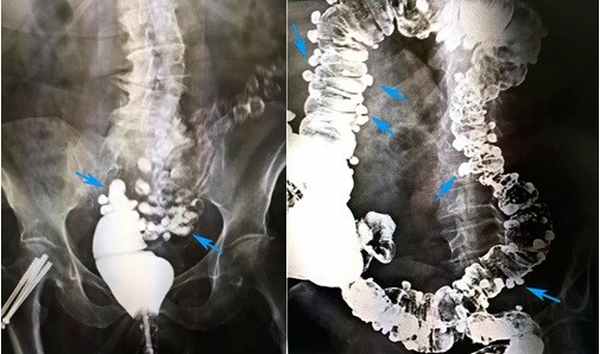

«Золотым стандартом» диагностики дивертикулярной болезни является ирригоскопия. Этот метод позволяет определить количество дивертикулов, их точное местоположение, размеры и форму. Суть процедуры заключается в введении рентгенконтрастного препарата в толстую кишку, после этого выполняется серия рентгенологических снимков, позволяющих оценить состояние толстой кишки. На представленных фотографиях стрелками указаны устья дивертикулов толстой кишки. Синими стрелками мы отметили множественные дивертикулы ободочной кишки. Именно так они выглядят при компьютерной томографии.

Рисунок 4. Ирригоскопия. Дивертикулез толстой кишки

На рентгенологических снимках, выполненных при ирригоскопическом исследовании, отчетливо видны множественные дивертикулы ободочной кишки. Они выглядят как мешочки, заполненные рентгеноконтрастным препаратом.